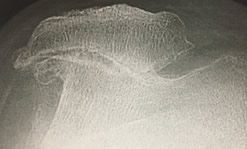

Arthrose fémoro-patellaire ou rotulienne

Dessin sur radio montrant le contact des deux os dans cette arthrose rotulienne

Arthrose évoluée fémoro-patellaire, rotulienne, externe